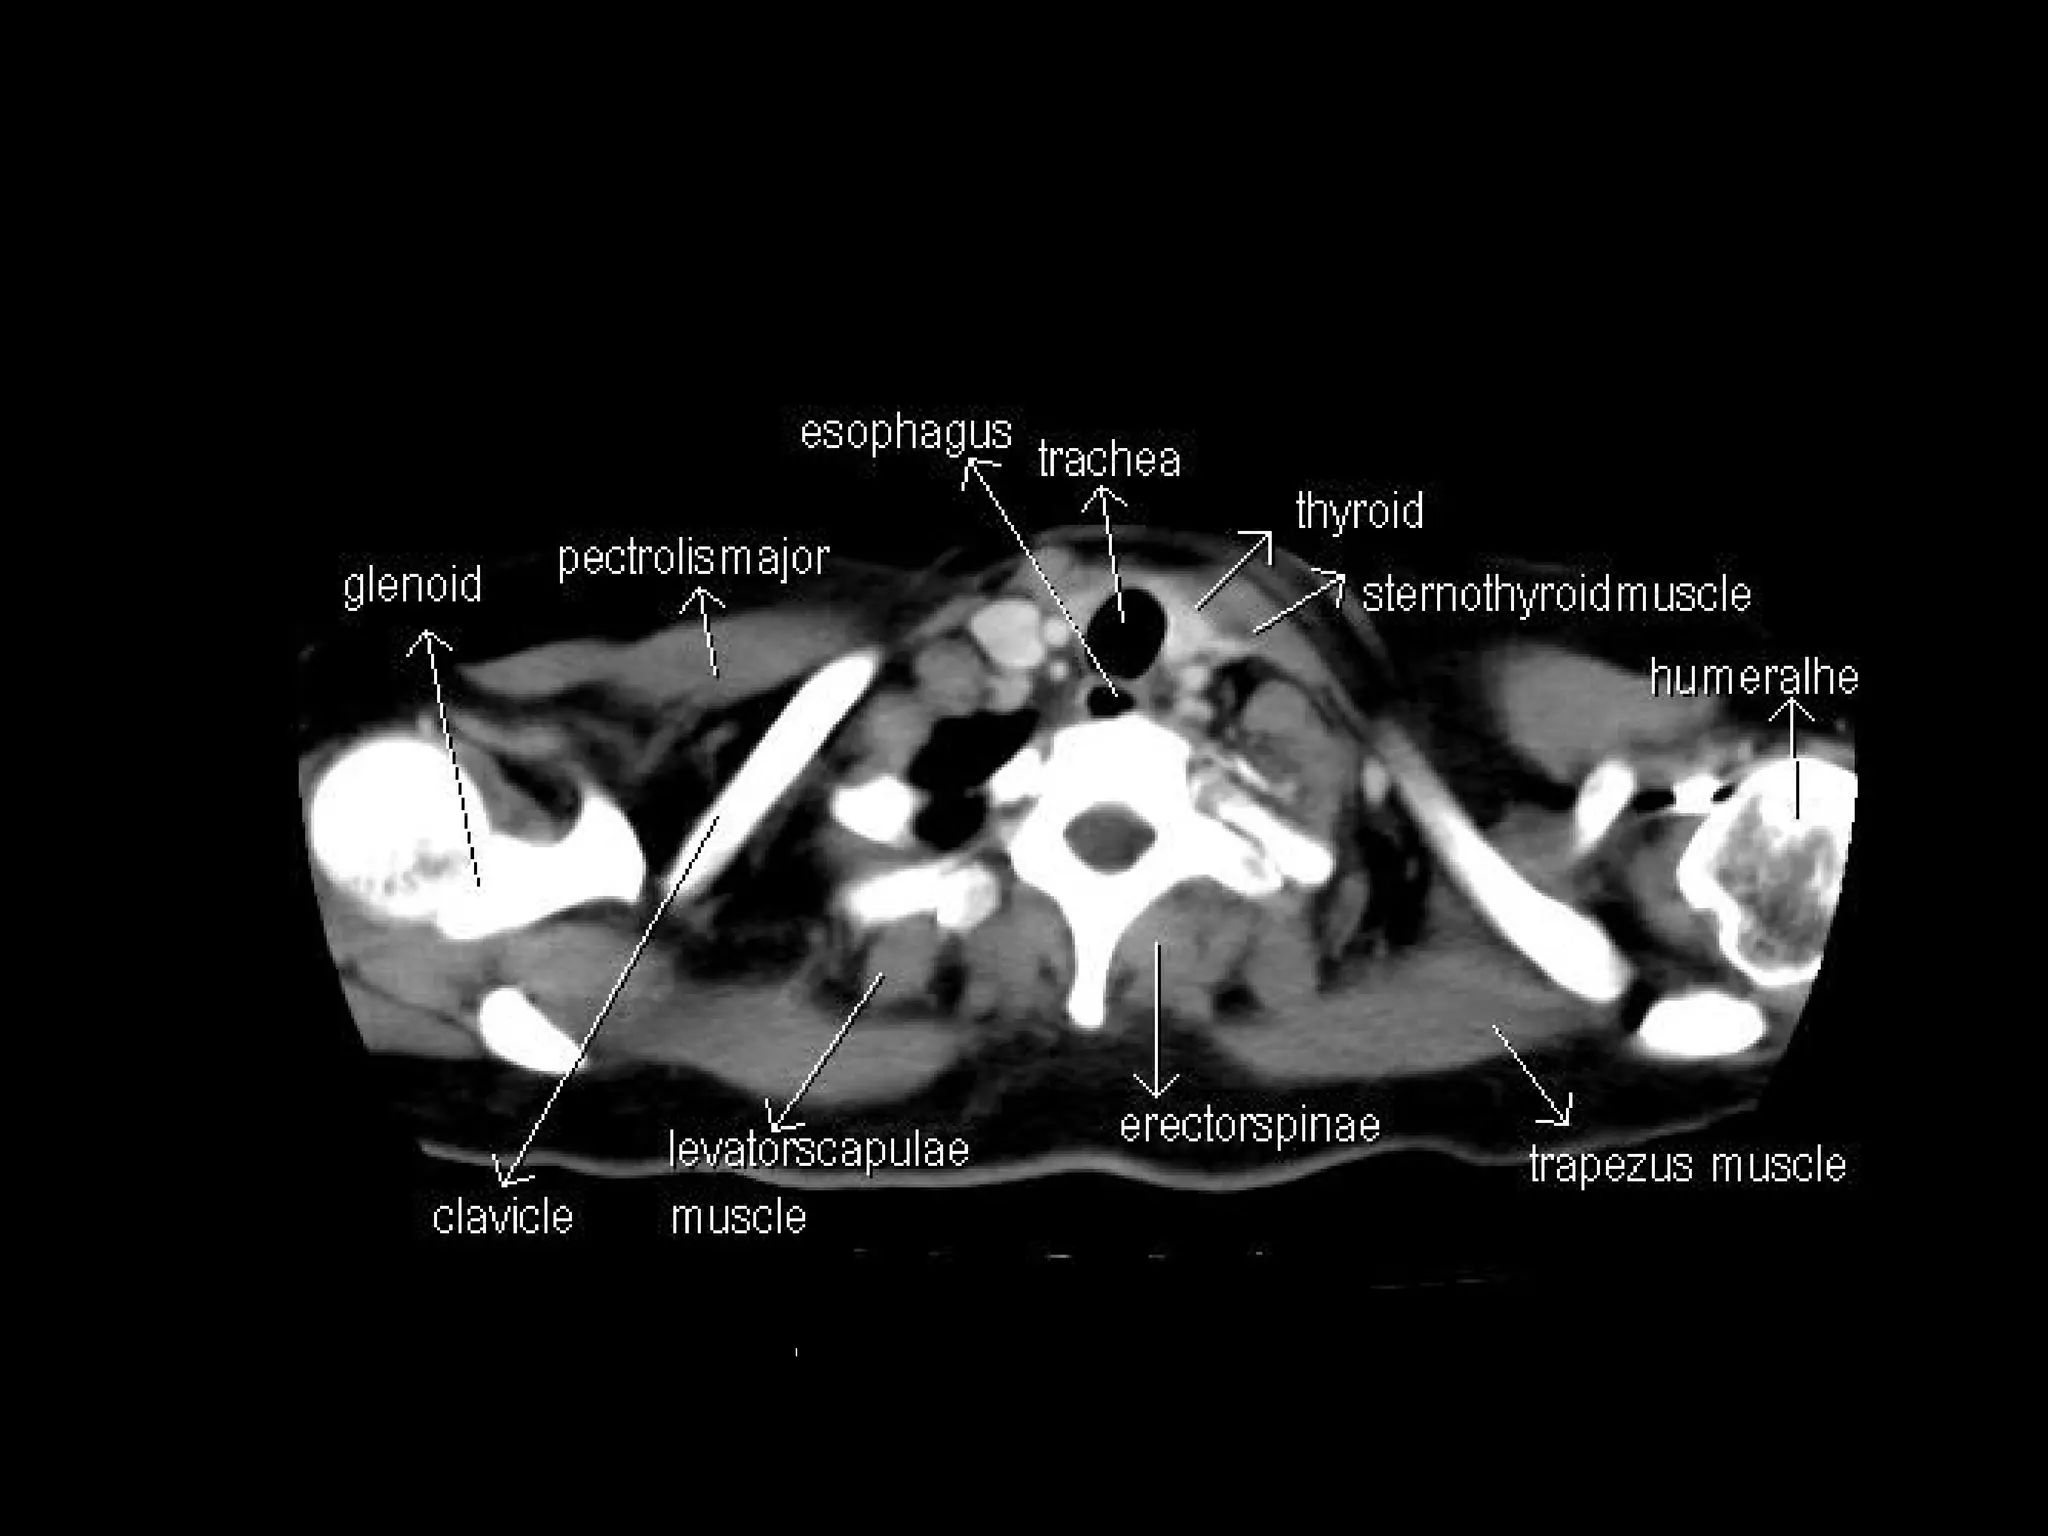

Radiographers are medical professionals who perform diagnostic imaging examinations and procedures to help physicians diagnose and treat diseases. They work under the supervision of radiologists to operate X-ray, CT, MRI, ultrasound and other medical imaging equipment and must have a strong understanding of human anatomy and pathology. Radiographers are responsible for correctly positioning patients, ensuring proper imaging techniques are used, and evaluating the quality of the resulting images.